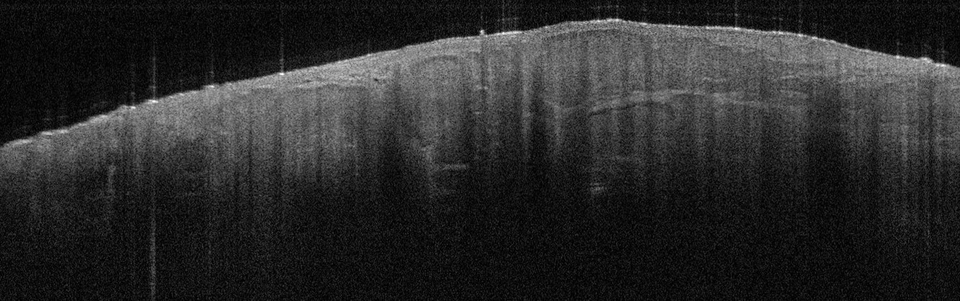

Die Tumorzellverbände des BCC erkennt man in der Aufnahme als signalarme, ovoide Nester mit dunk­lem Randsaum, die von hellem Stroma umgeben sind. Die Epidermis ist abgeflacht, Teleangiektasien kann man als kleine dunkle Löcher sehen. Eine aktinische Keratose sieht anders aus: In diesem Fall sind Hornschicht und Epidermis verdickt, oft sieht man auch weiße Streifen in der Hornschicht, so die Referentin. In Abgrenzung zum Plattenepithelkarzinom erscheint die dermoepidermale Junktion bei der aktinitischen Keratose intakt. Beim Plattenepithelkarzinom werden zudem helle Bereiche deutlich, bei denen es sich um Hornzysten handelt.

Beim nodulären BCC zeigen sich die typischen ovoiden knotigen Tumorzellverbände. Die über dem BCC liegende Epidermis ist verdünnt. Beim nodulären BCC zeigen sich die typischen ovoiden knotigen Tumorzellverbände. Die über dem BCC liegende Epidermis ist verdünnt. © Prof. Dr. Julia Welzel